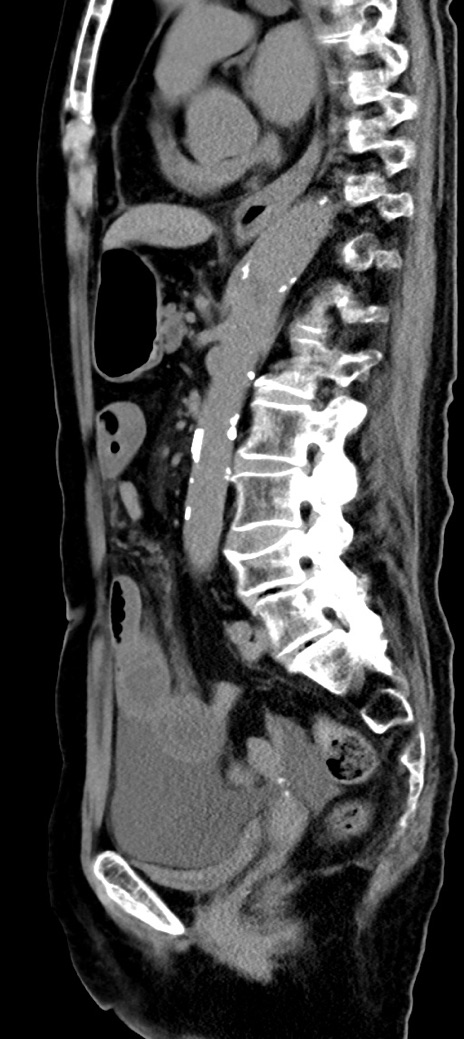

横断像

【症例】90歳代女性

【主訴】腹痛・嘔吐

【現病歴】 食欲低下、嘔吐があり昨日他院受診。肺炎と診断され入院となる。入院後より腹部全体に圧痛あり。胃管留置され経過みていたが、症状持続するため、

当院転院となる。

【既往歴】胸椎圧迫骨折、胆石症

【身体所見】腹部:中央に激痛あり、圧痛あり、反跳痛不明

【データ】WBC 17100、CRP 18.82